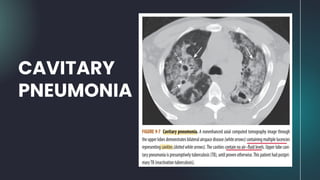

● The prototypical organism produciing cavitary pneumonia is

Mycobacterium tuberculosis.

● Cavitation is common in postprimary tuberculosis (TB)

(reactivation tuberculosis) but rare in primary TB.

● The cavities are usually located in the upper lobes, are

bilateral and thin-walled, have a smooth inner margin, and

contain no air-fluid level.

● Transbronchial spread may be suggestive of infection with

CAVITARY PNEUMONIA

● The prototypicalorganism produciing cavitary pneumonia is Mycobacterium tuberculosis. ● Cavitation is common in postprimary tuberculosis (TB) (reactivation tuberculosis) but rare in primary TB. ● The cavities are usually located in the upper lobes, are bilateral and thin-walled, have a smooth inner margin, and contain no air-fluid level. ● Transbronchial spread may be suggestive of infection with Mycobacterium tuberculosis. CAVITARY PNEUMONIA